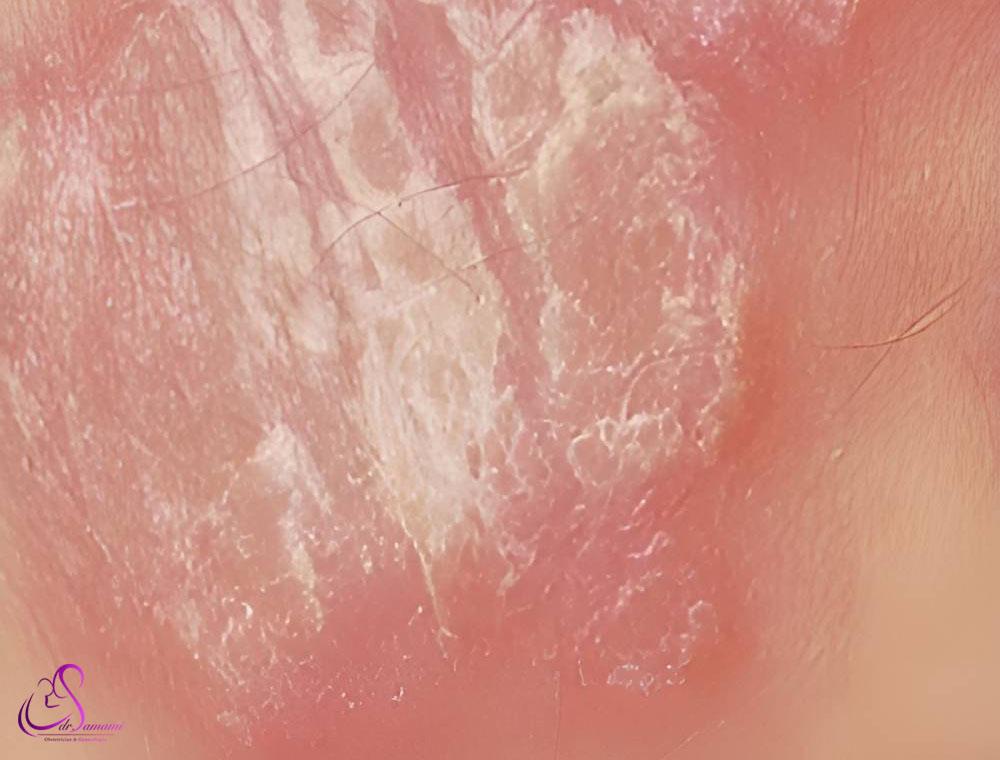

پسوریازیس

پسوریازیس یک بیماری پوستی خودایمنی است که باعث ایجاد سلولهای پوستی اضافی شده و در نهایت منجر به ایجاد ضایعات قرمز، ضخیم و پوسته پوسته میشود. پسوریازیس میتواند لابیاهای مینور و ماژور را تحت تأثیر قرار دهد و علت دقیق آن ناشناخته است، اما عوامل متعددی از جمله ژنتیک، سیستم ایمنی، عفونت، داروها و استرس میتوانند در ابتلا به آن نقش داشته باشند. در صورت مشاهده هر یک از علائم زیر، مراجعه به پزشک و آغاز درمان ضروری است.

- ضایعات قرمز، ضخیم و پوسته پوسته: این ضایعات ممکن است روی لابیاهای مینور، ماژور یا هر دو ایجاد شوند.

- خارش، سوزش یا درد: ضایعات ممکن است خارش، سوزش یا درد داشته باشند.

- ترک خوردگی یا خونریزی: در موارد شدید، ضایعات ممکن است ترک خورده یا خونریزی کنند.

- دشواری در رابطه جنسی: ضایعات ممکن است رابطه جنسی را دشوار یا دردناک کنند.